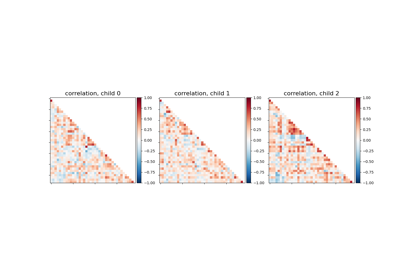

Classification of age groups using functional connectivity